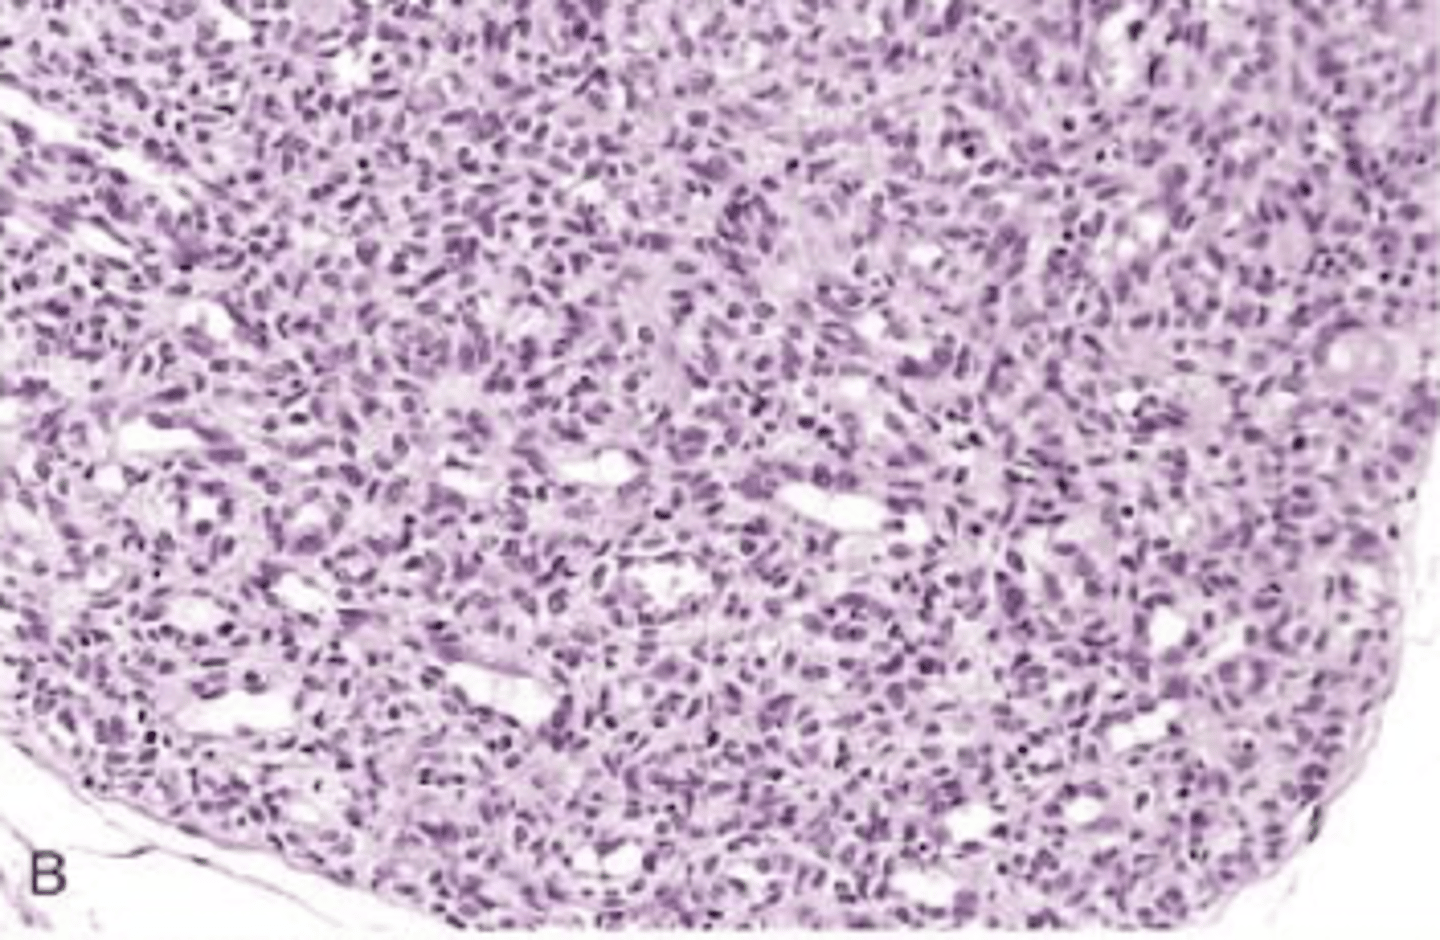

kaposi sarcoma

vascular neoplasm caused by HHV-8

kaposi sarcoma is associated with

AIDS

s/s of kaposi sarcoma

3 stages of cutaneous lesions in LE

1. patches

2. raised plaques

3. nodular

AIDS-associated KS

most common HIV related malignant worldwide